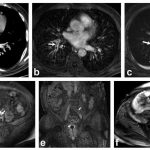

Bir dönem Denizli Tekden Hastanesinde de çalışan ve çalışmalarına ABD’de devam Dr. Nevzat Karabulut ve ekibinin yaptığı, British Journal of Radiology dergisinde yayımlanan “Diagnostic performance of contrast-enhanced and unenhanced combined pulmonary artery MRI and magnetic resonance venography techniques in the diagnosis of venous thromboembolism” başlıklı araştırmada manyetik rezonans (MR) yöntemi kullanılarak hem akciğer damarlarının hem de pıhtının kaynağı olan bacak toplardamarlarının aynı anda, tek bir incelemede değerlendirilebileceği gösterildi. Toplam 44 hastanın incelendiği çalışmada elde edilen sonuçlar oldukça dikkat çekti.

Kontrastlı MR yöntemi, hastaların tamamında akciğer embolisini doğru şekilde tespit ederken; kontrastsız MR yöntemi de yüksek doğruluk oranına ulaştı ve önemli ölçüde güvenilir sonuçlar verdi. Bu bulgular, radyasyon içermeyen MR yönteminin pıhtı hastalığını saptamada güçlü bir alternatif olduğunu ortaya koydu. Özellikle Radyasyon riskinin daha önemli olduğugenç hastalarda ve gebelerde MR’ın güvenli ve etkili bir seçenek olabileceği vurgulandı.